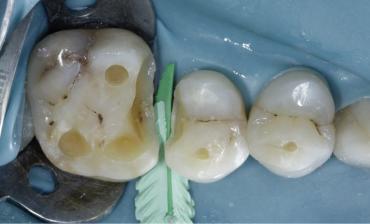

Figure 01: Composite restoration placed in adjacent defects without use of any sectional matrix system. Occlusal erosion facets seen due to acid reflux with flat anatomy of the teeth.

Figure 04: Caries end point removal, achieving peripheral seal zone, Removing unsupported enamel, . The picture was taken after air abrasion and selective etching was performed. Garrison Strata G Firm wedge placed as prewedging to protect rubber dam.